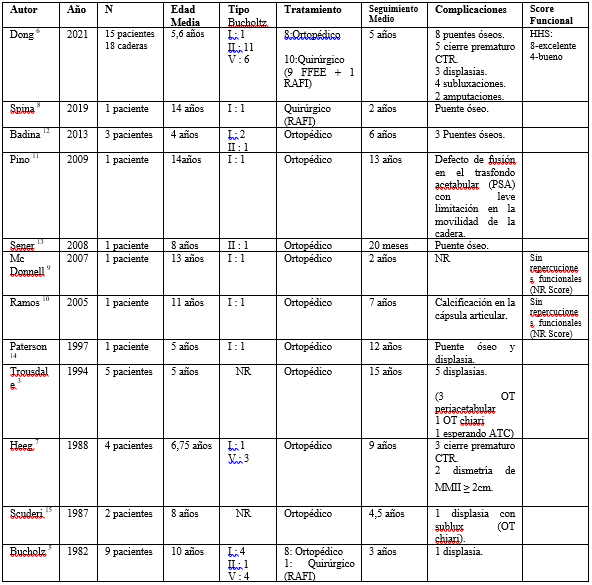

Las lesiones traumáticas del cartílago trirradiado son infrecuentes, habiendo pocos casos descriptos en la literatura. La mayoría son reportes de caso, las dos series más grandes encontradas son la de Dong6 del 2021, que registra 15 niños con 18 lesiones acetabulares en su hospital en China, con cinco años de seguimiento promedio; y la reportada por Bucholz5, publicada en 1982, de nueve pacientes con un seguimiento promedio de tres años.

En la tabla 1 se detalla los casos hallados en la literatura. La edad promedio fue de 8,7 años, similar a la edad reportada en nuestro caso (9 años). El mecanismo traumático de la mayoría de los casos fue relacionado a accidentes de tráfico, no obstante, el mecanismo lesional de nuestra paciente fue de baja energía cinética.

Tabla 1: Revisión de casos de lesiones acetabulares con compromiso del cartílago trirradiado hallados en la literatura.

n: numero de casos. RAFI: reducción abierta y fijación interna. FFEE: fijadores externos. NR: no reporta. CTR: cartílago trirradiado. HHS: Harris Hip Score. PSA: pseudoartrosis. OT: osteotomía. ATC: artroplastia total de cadera. MMII: miembros inferiores.

La distribución según la clasificación de Bucholz fue similar, 13 lesiones tipo I, 13 lesiones tipo V, y 14 tipo II como en nuestro caso. La mayoría de las lesiones fueron tratadas ortopédicamente, mediante reposo en cama y/o tracción esquelética por 4 a 8 semanas, comenzando luego con un plan de apoyo parcial y progresivo.

Recientemente Spina8 en 2019, reportó el caso de un niño de 14 años con una fractura tipo I tratada quirúrgicamente mediante fijación interna sin complicaciones clínicas ni radiológicas con un seguimiento de 2 años.

El caso publicado por McDonnell9 de un niño de 13 años con una fractura con compromiso del cartílago trirradiado, sin desplazamiento, tipo I de Bucholz, tratado ortopédicamente no registró deformidades residuales ni arrestos fisarios con un seguimiento de 2 años.

Ramos y cols. (10 en el 2005, reportaron un caso similar de una niña de 11 años con una lesión tipo I tratada con tracción de partes blandas por 6 semanas sin secuelas funcionales ni radiológicas a los 7 años del episodio.

Por otro lado Pino y cols11 describen en su trabajo a un niño de 14 años con un fractura tipo I de Bucholz tratada ortopédicamente, que tras 13 años de seguimiento presenta una leve limitación de 10° a la flexión cadera y 20° de rotación interna, molestias solo con los movimientos extremos pero que no le limita las actividades de la vida diaria.

Trousdale y Ganz3) en su serie de 5 pacientes esqueléticamente inmaduros con fracturas acetabulares tratados ortopédicamente desarrollaron displasia postraumática severa, 4 de ellos requiriendo osteotomías correctoras en la adultez y el restante en espera de una artroplastia de cadera.

Al igual que en trabajo de Heeg7 los tres de los pacientes con lesiones tipo V sufrieron alteraciones en el crecimiento del acetábulo que requirieron en la evolución osteotomías reconstructivas.

Dong6 registra la serie más grande con 18 fracturas acetabulares tratando 10 quirúrgicamente, 9 con FFEE y una mediante reducción abierta y fijación interna; las restantes 8 lesiones fueron tratadas ortopédicamente. Con un seguimiento promedio de 5 años reportó varias complicaciones, incluidas 2 amputaciones altas que no continuaron en el estudio. Sin embargo, en los 12 pacientes restantes se obtuvieron mediante HHS 8 pacientes con resultados excelentes y 4 buenos resultados.